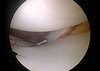

An 18-year-old man sustains a twisting injury to the left knee while playing football. An MRI scan is shown in Figure 48. What is the most likely diagnosis?

MRI scan shows a displaced, bucket-handle lateral meniscus tear. The sagittal view shows the typical “large anterior horn” sign, or “double meniscus” sign in which the displaced bucket-handle fragment appears just anterior to the native anterior horn of the lateral meniscus. The presence of the fibula on the sagittal view confirms this as the lateral compartment. The image is lateral and the cruciate ligaments are not visualized. The articular cartilage shown does not demonstrate an osteochondral lesion.